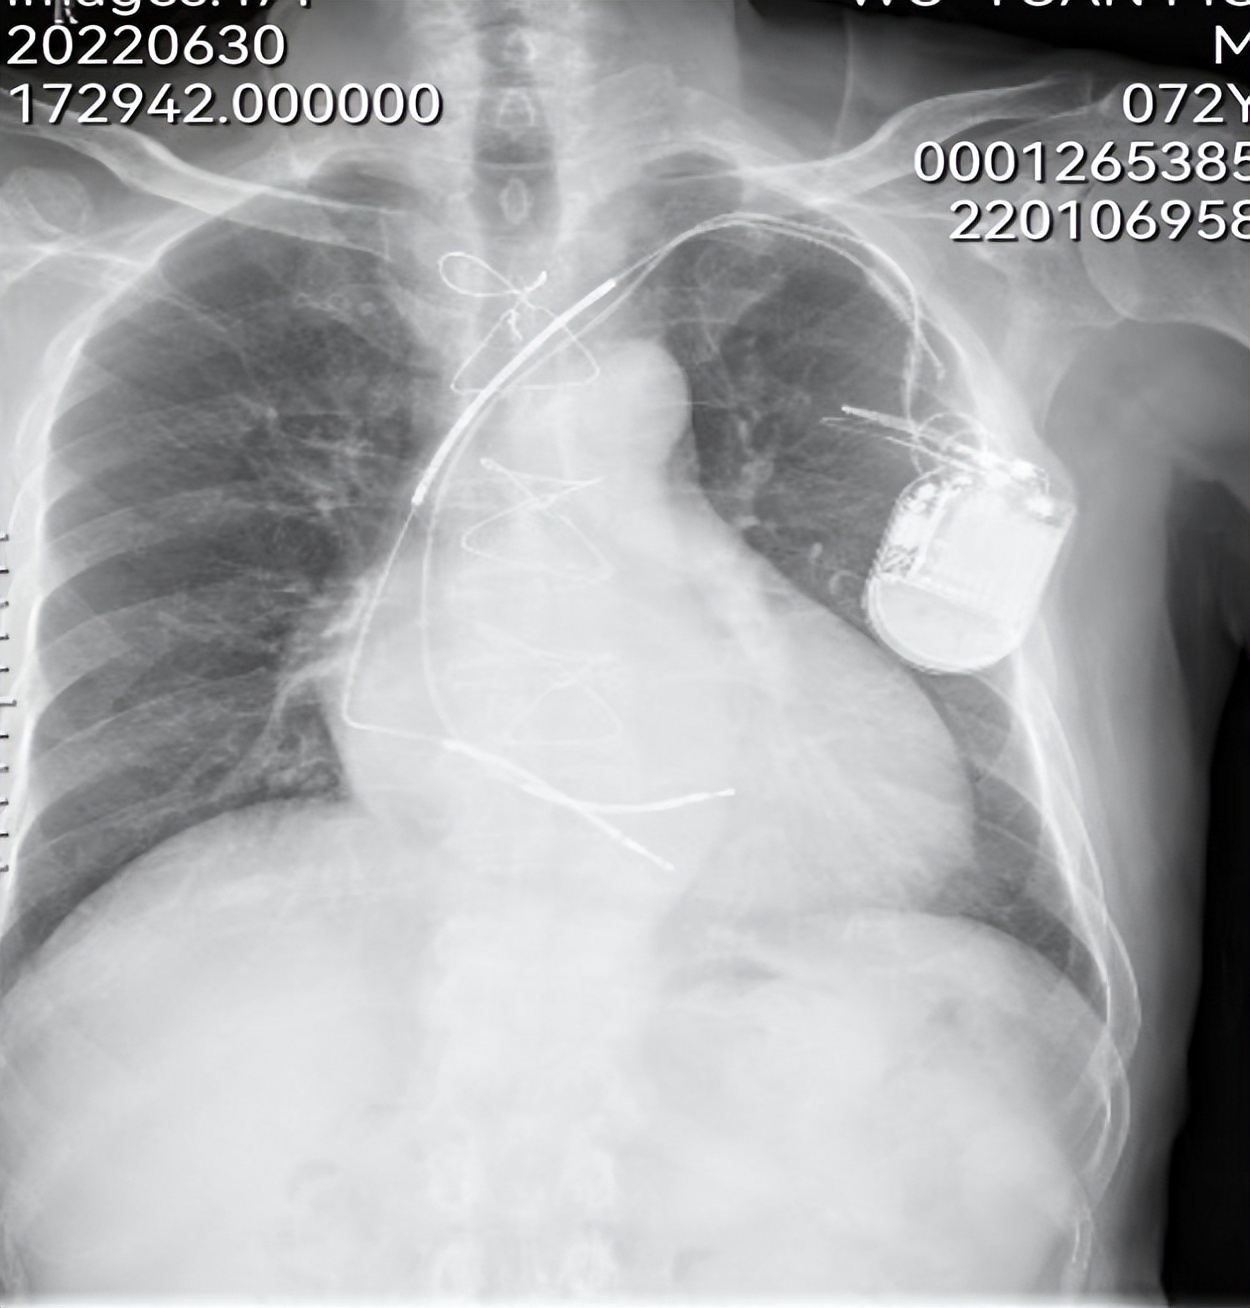

术前胸片

一年前因除颤器电池耗竭和除颤电极故障,邬先生在当地医院行除颤器更换+新电极除颤电极植入,20天前除颤器囊袋出现感染,除颤电极外露于皮肤外,有脓性分泌物渗出,上转入省人民医院诊治。经起搏器治疗团队反复研究病情,考虑患者ICD已植入9年,且囊袋感染,最好的办法是行ICD及除颤电极移除。但患者体内有两根电极,植入近9年,去年ICD更换时曾试图拔电极,未能拔除,说明电极与上腔静脉及瓣环粘连较重。遂决定采用经上、下腔静脉联合方法拔除电极。7月7日下午,经周密准备,成功为患者拔除两根除颤电极,手术过程顺利,为患者节省了7-8万元的手术费,患者家属对此万分感谢。